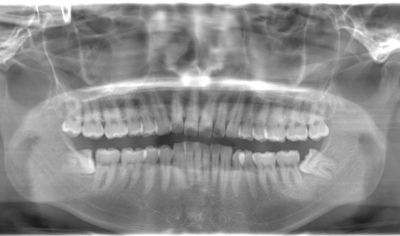

抜歯後に麻痺や腫れなどもなく経過良好です。

治療前パノラマ

抜歯前

抜歯後

抜歯後

| 年齢・性別 | 20代・男性 |

|---|---|

| 主訴 | 主訴:左下の親知らずが4年前位から時々痛みがあり気になるので抜歯したい。 治療部位:左下親知らず |

| 治療内容 | 左下8番 |

| 治療期間 | 60分 |

| 治療費 | ・合計約5,000円 ・保険診療3割負担 抜歯代約2,000円 ・CT算定代 約3,000円 (2024年1月現在) |

| リスク・副作用 | ・治療後2.3時間程度麻酔が効いています。 ・抜歯後2.3日をピークに腫れや痛み、発熱、口が開きにくいなどの症状が出ることがあります。 ・強くゆすぐとカサブタが剥がれて激しい痛みがでるので優しくゆすぐようにしてください。 ・当日は飲酒や入浴、激しい運動など血流の良くなることは控えていただきます。 ・下顎の親知らずは骨の中を通っている血管、神経や舌の神経に近接しているため術後に下唇や舌の知覚異常を起こす可能性があります。 |

| 治療方針 | 半分歯ぐきに埋まっていた歯だったため、CTを撮影し神経との距離や生え方を確認してから抜歯しました。 |

| 特記事項 | 切開しましたが歯の骨を削らずに抜歯できました。 |

| 担当者所見 | 抜歯後に麻痺や腫れなどもなく経過良好です。 |